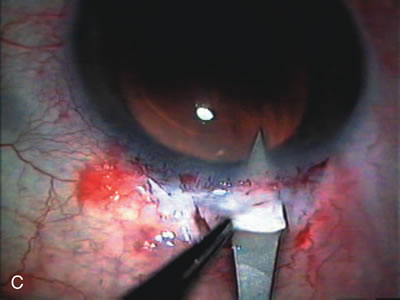

Cataract extraction by any technique performed in a patient with a pre-existing filter will have an effect on the previous filtering bleb.121–124 Bleb failure is more likely with ECCE compared with small-incision phacoemulsification.125 However, even patients undergoing topical anesthesia with clear corneal phacoemulsification and foldable IOL may experience bleb failure. One of three patients with a functioning filter and preoperative mean IOP of 12 mm Hg without antiglaucoma medications experiences bleb failure after lens extraction (Table 2). These patients require long-term drug therapy or bleb needling to control IOP. 126 Additional incisional glaucoma surgery may eventually be required in up to 10% of patients.127 Intraoperative iris manipulation may cause significant breakdown of the blood–aqueous barrier, resulting in inflammation that causes bleb failure. Even after uncomplicated clear corneal phacoemulsification, IOP may increase an average of 2 to 3 mm Hg due to bleb fibrosis.128 Approximately 20% of filtered patients require a long-term increase in glaucoma medications following uncomplicated clear corneal phacoemulsification with a foldable copolymer acrylic IOL129 (Fig. 3). In situations in which the bleb is not working at all, the eye will have a postoperative pressure spike that mimics that in the patient not having had a prior filtering procedure. In situations in which the bleb is marginal, the pressure spikes tend to be lower, and the final postoperative IOP tends to be around 50% higher than it was preoperatively. These patients require combined procedures in order to reestablish long-term filtration. In situations in which the bleb is very thin, polycystic, and associated with an IOP around 5 to 8 mm Hg on no antiglaucoma therapy; uncomplicated cataract extraction will have a minimal effect on the level of IOP. Patients with functioning glaucoma drainage implants usually have minimal long-term changes in IOP after uncomplicated cataract extraction.130

Fig. 3. Partial bleb failure following clear corneal phacoemulsification with foldable IOL. A. Preoperative bleb appearance prior to temporal lens extraction. Preoperative IOP was 12 mm Hg on no antiglaucoma medications. Time from 5-FU trabeculectomy surgery to lens extraction was one year. B. Bleb appearance 2 months after clear corneal cataract surgery with topical anesthesia. Following lens extraction, increased vascularity was noted along with decreased size of the filtering bleb. IOP increased to 20 mm Hg as early as 2 weeks after surgery, necessitating topical antiglaucoma therapy. C. High magnification view of bleb before lens extraction demonstrates diffuse pale bleb. D. High magnification view of bleb 2 months after surgery. There are vessels surrounding the nasal side of the bleb and the overall bleb size is smaller.